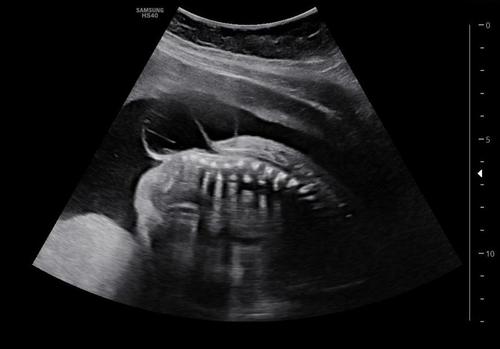

De acuerdo con información de Stereo100, en Quetzaltenango, un grupo de médicos llevó a cabo una intervención quirúrgica a un bebé cuando todavía estaba en el útero, para corregir espina bífida. Según los especialistas, es la primera cirugía de este tipo que se realiza en Centroamérica.

El procedimiento quirúrgico se llevó a cabo el 5 de mayo en el Centro Médico La Paz de Occidente, con un equipo integrado por especialistas en medicina materno fetal, un neurocirujano y anestesiólogas obstétricas, quienes realizaron la corrección de espina bífida al feto, dentro del útero de la madre.

Dos días después, el 7 de mayo, se llevó la cesárea para el alumbramiento de Andrés, como fue llamado por sus padres. Según los médicos, el bebé nació sin complicaciones con un peso de casi cinco libras y 45 centímetros de talla.